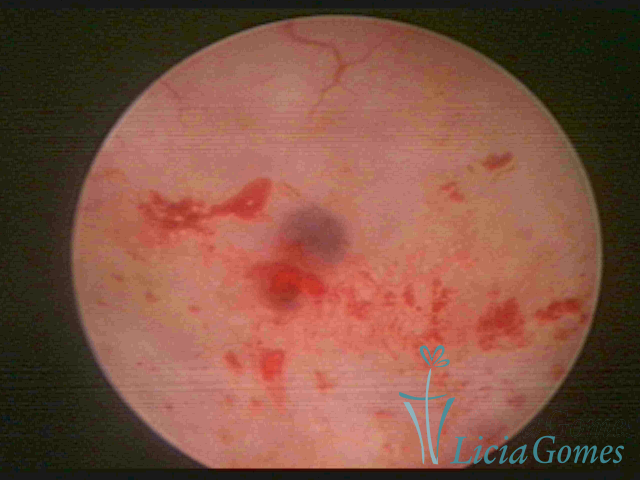

ADENOMYOSIS

The presence of endometrial tissue on the muscular layer of the uterus.

Video hysteroscopy allows diagnosing the lesions next to the superficial myometrial layers next to the endometrium, allowing the view of in situ, purplish, or chocolate brown lesions.